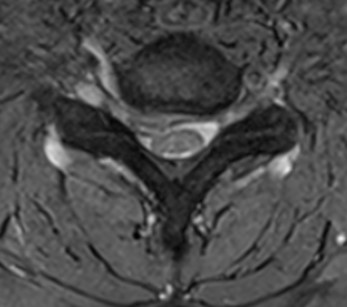

Yapılan MRG incelemelerinde (aşağıdadı) C6-7 seviyesinde bir disk hernisi saptandı.

Hastaya skopi kontrolü altında sağ C6-7 seviyesinden transforaminal epidural enjeksiyon uygulandı.